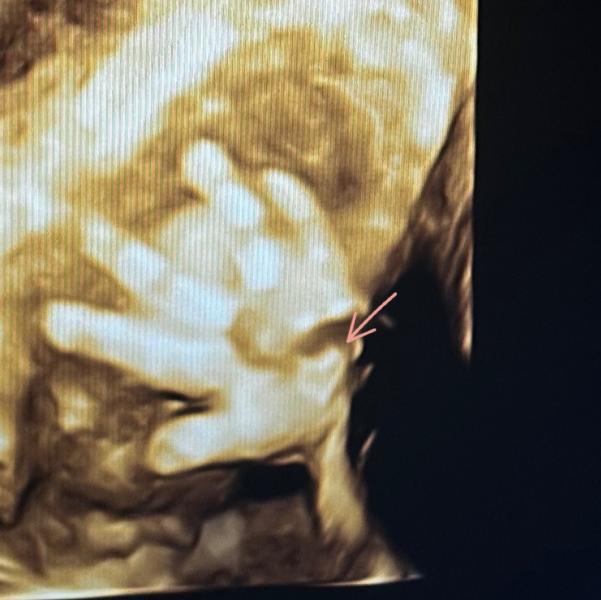

Дочка показала сердечко на УЗИ: трогательный момент

Дочка показала нам сердечко💗